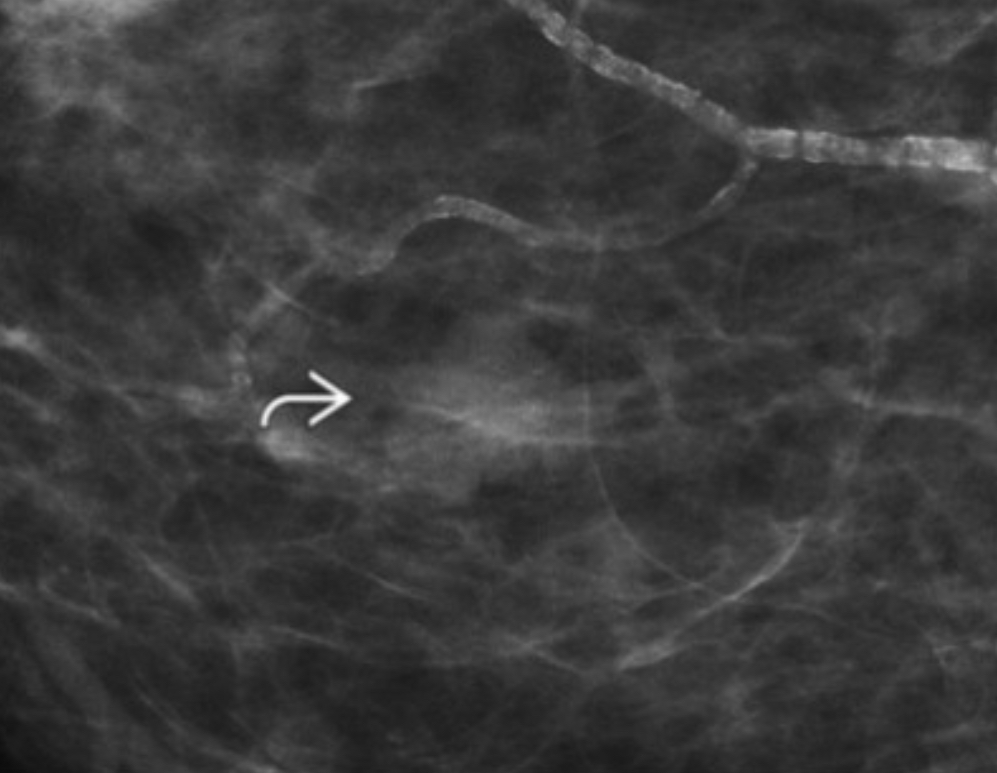

What do you expect to find on US?

Clustered microcysts

we see a lobular mass with microlobulated borders, isodense with no fat internally